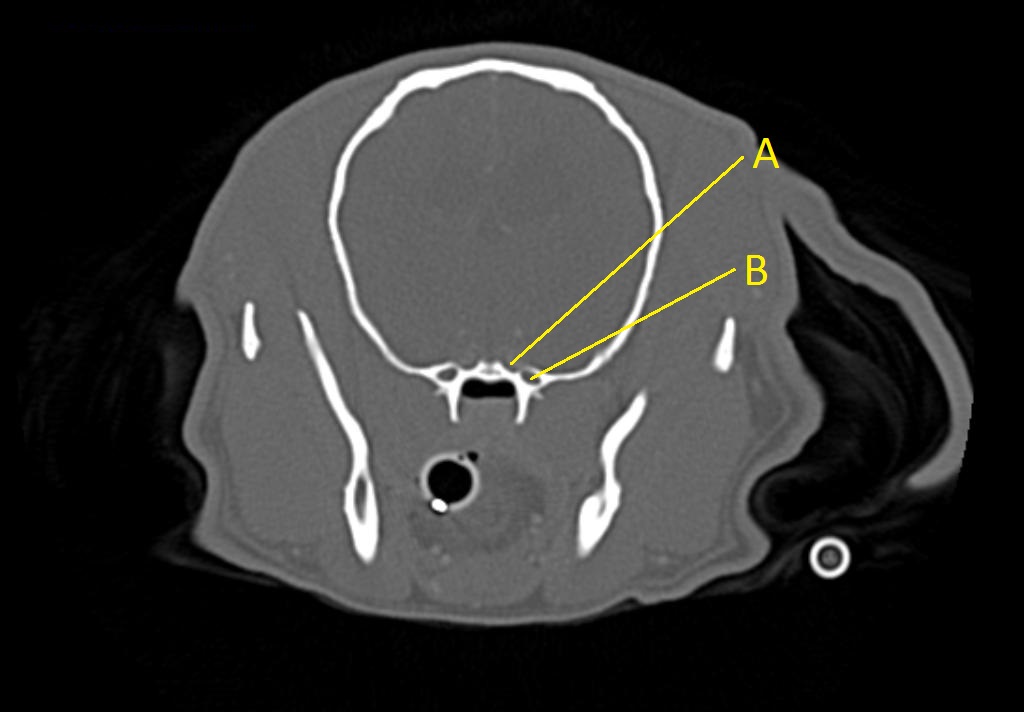

Q. Identify the structures labeled below:

A. orbital fissure

B. alar canal